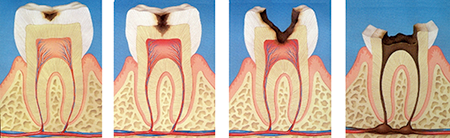

In "dental caries, "mutans bacteria adhere on the tooth surface and produce acid from sugar.

This causes the teeth to dissolve and cold or hot foods begin to sting.

If the tooth becomes severely decayed, it can reach the pulp inside the tooth, causing pain even when you're not doing anything.

Bacteria that have reached the pulp will travel through the root canal, the cavity where the pulp used to be, to the the root apex, and finally proliferate in the bone that supports the tooth (Fig. 8).